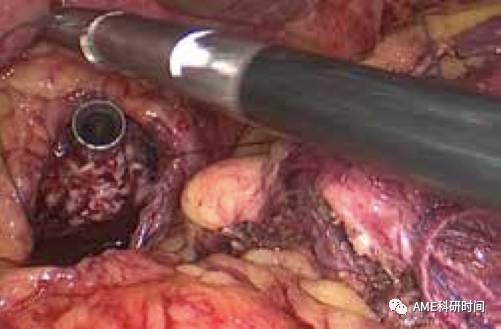

注:在Mayo Clinic学习时,发现外科医师均采用丝线进行精确测量,认为非常可取。 2食管空肠吻合:从已扩大的左上腹腋前线主操作孔放置F18号切口保护圈,置入管型吻合器杆把,将保护圈包绕吻合器并旋转、向外提拔,避免气腹漏气(如图33);远端空肠置入管型吻合器,与食管下端的钉座吻合(如图34-35), 留置或不留置胃管至空肠Y襻,空肠盲端用直线切割闭合器闭合。

图33 保护圈包绕

图34 置入弯管吻合器

图35 与钉钻头嵌合

注:1)吻合时特别需要助手反向牵拉吻合口输出端肠管(如图36),避免吻合肠管重叠,造成输出肠管钉闭的严重并发症(如图37);2)本步骤中,在腹腔外把空肠套入管型吻合器,并用丝线捆绑也是可行的方法(如图38)。但需要较大的辅助切口、游离过多Roux-en-Y肠袢、手术步骤复杂化,也出现过回纳腹腔时肠管脱落和击发后丝线不能割断的情况。3)采用完全腹腔内置入并管型吻合器(F25号)进行吻合,均可顺利快捷完成。4)吻合完成后,建议放入胃管、或用剥离子通过空肠残端检查吻合口。